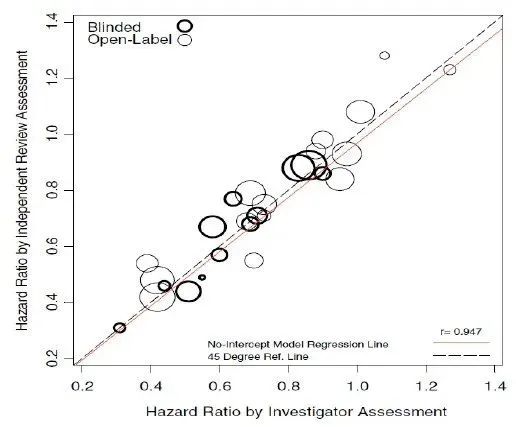

иҮідәҺз ”з©¶иҖ…иҜ„дј°е’ҢIRCиҜ„дј°еӯ°дјҳеӯ°еҠЈ����пјҢжңүMetaеү–жһҗеҸ‘жҳҺ����пјҢз ”з©¶иҖ…иҜ„дј°е’ҢIRCиҜ„дј°е…ідәҺPFSж•Ҳжһңзҡ„иҜ„дј°е…·жңүй«ҳеәҰдёҖиҮҙжҖ§����пјҢзӣёе…ізі»ж•°еҸҜиҫҫ0.947пјҲеӣҫ4пјү[14]��гҖӮеӣ жӯӨеҸҜеңЁйҖүжӢ©дёҖж–№иҜ„дј°ж•ҲжһңдҪңдёәдё»иҰҒз»ҲзӮ№зҡ„еҗҢж—¶е°ҶеҸҰдёҖж–№дҪңдёәж¬ЎиҰҒжҲ–иҖ…дёҫиЎҢж•Ҹж„ҹжҖ§еү–жһҗ����пјҢдёӨиҖ…зӣёдә’жҜ”з…§гҖҒй…ҚеҗҲз»„жҲҗз ”з©¶зҡ„еҸҢеҢ…з®Ў����пјҢ并еңЁиҫғйҮҸз ”з©¶иҖ…иҜ„дј°дёҺIRCиҜ„дј°ж•Ҳжһңж—¶еҸҜе…іжіЁеҚұе®іжҜ”пјҲHazard Ratio����пјҢHRпјүе’ҢPеҖј��гҖӮCDEеңЁгҖҠжҠ—иӮҝзҳӨиҚҜдёҙеәҠиҜ•йӘҢеҪұеғҸиҜ„дј°зЁӢеәҸж ҮеҮҶжүӢиүәжҢҮеҜјеҺҹеҲҷпјҲ2021е№ҙпјүгҖӢдёӯжҸҗеҲ°����пјҢдёҚиҝҮеәҰејәи°ғIRCдёҺз ”з©¶иҖ…еңЁжңҖз»ҲиҜ„дј°ж•Ҳжһңзҡ„дёҖиҮҙжҖ§����пјҢдҪҶйңҖзӣ‘жҺ§дёӨиҖ…иҜ„дј°ж•Ҳжһңд№Ӣй—ҙе·®еҲ«зҡ„зЁіеӣәжҖ§[15]��гҖӮеңЁгҖҠжҠ—иӮҝзҳӨиҚҜзү©дёҙеәҠиҜ•йӘҢз»ҹи®ЎеӯҰи®ҫи®ЎжҢҮеҜјеҺҹеҲҷпјҲиҜ•иЎҢпјүгҖӢдёӯд№ҹжҢҮеҮә“з ”з©¶иҖ…е’ҢBICRеҜ№з–ҫз—…еёҢжңӣиҜ„дј°зҡ„е·®еҲ«жҖ§жҳҜPFSеү–жһҗдёӯзҡ„дё»иҰҒй—®йўҳ����пјҢеҜ№PFSеү–жһҗж—¶����пјҢеә”йҖҡдҫӢеҜ№жӯӨе·®еҲ«жҖ§дёҫиЎҢеү–жһҗ����пјҢ并иҜ„д»·е…¶еңЁз»„й—ҙжҳҜеҗҰе№іиЎЎ”[16]��гҖӮ

еӣҫ4. з ”з©¶иҖ…иҜ„дј°е’ҢIRCиҜ„дј°е…ідәҺPFSж•Ҳжһңзҡ„дёҖиҮҙжҖ§еү–жһҗ

еҮӯиҜҒCDEзҡ„гҖҠжҠ—иӮҝзҳӨиҚҜдёҙеәҠиҜ•йӘҢеҪұеғҸиҜ„дј°зЁӢеәҸж ҮеҮҶжүӢиүәжҢҮеҜјеҺҹеҲҷпјҲ2021е№ҙпјүгҖӢ����пјҢеҚ•иҮӮи®ҫи®Ўзҡ„жӢҹж”ҜжҢҒжіЁеҶҢз ”з©¶зӣ®д»ҠйЎ»жҺҘзәіBICRиҜ„дј°����пјҢиҖҢеңЁеҸҢзӣІйҡҸжңәжҜ”з…§зҡ„еӨ§еһӢIIIжңҹи®ҫи®Ўзҡ„дёҙеәҠиҜ•йӘҢдёӯ����пјҢBICRиҜ„估并йқһеҝ…йңҖ[15]��гҖӮFLAURAе’ҢAENEASеқҮеҲҮеҗҲдёҠиҝ°йқһеҝ…йңҖиҰҒжұӮ����пјҢеңЁеҸҢзӣІи®ҫи®ЎдёӢиғҪеҫҲеҘҪең°жҺ§еҲ¶еҒҸеҖҡ����пјҢе°Ҷз ”з©¶иҖ…иҜ„дј°зҡ„PFSдҪңдёәдё»иҰҒз»ҲзӮ№зҡ„еҗҢж—¶д№ҹе°ҶIRCиҜ„дј°зҡ„PFSзәіе…Ҙж¬ЎиҰҒз»ҲзӮ№����пјҢ并еҜ№еҹәдәҺIRCиҜ„дј°зҡ„ж•ҲжһңдёҫиЎҢдәҶж•Ҹж„ҹжҖ§еү–жһҗпјҡеңЁFLAURAе’ҢAENEASдёӯ����пјҢз ”з©¶иҖ…иҜ„дј°е’ҢIRCиҜ„дј°зҡ„ж•Ҳжһңе…·жңүеҫҲеҘҪзҡ„дёҖиҮҙжҖ§����пјҢдё”з ”з©¶иҖ…зҡ„дёӯдҪҚPFSз•ҘеҘҪдәҺIRCиҜ„дј°����пјҢFURLONGеҲҷзӣёеҸҚ��гҖӮ